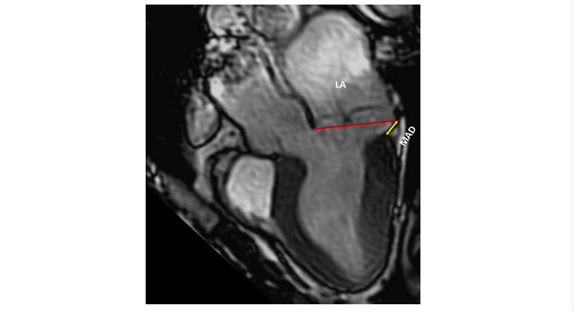

CMR serves as a pivotal tool in improving the stratification of arrhythmic risk and filling in the gaps in data that may be missing in echocardiography. (8).

Balanced steady-state free precession (bSSFP) cine sequences can thoroughly examine cardiac morphology and function, detecting LV remodelling signs.

As for echocardiography, it is imperative to document key mitral valve characteristics, including bileaflet MVP and myxomatous MVP. The assessment should encompass measurements of the mitral annulus at both end-systole and end-diastole in both anteroposterior and inter-commissural aspects. Additionally, factors such as leaflet diastolic thickness, leaflet length, prolapsed distance, and the presence or absence of systolic curling, if applicable, should be mentioned, and quantification is necessary (8).

A comprehensive evaluation of MAD around the mitral annulus involves acquiring six left ventricular long-axis cine sequences with a 30° interslice rotation. Assessing MAD severity typically requires measuring its longitudinal length, at least from the long-axis view, and possibly its circumferential extent expressed in degrees (8,9,10).

Moreover, CMR enables the calculation of MR volume and fraction thanks to phase-contrast velocity mapping sequences (5,6).

Lastly, CMR's unique capability lies in its ability to reveal information about the presence of myocardial fibrosis thanks to late gadolinium enhancement (LGE) images. In cases of MVP, fibrosis is frequently located near the annulus, primarily in the basal left ventricular wall, including the papillary muscles and inferior wall. Notably, only LGE within the mitral apparatus (papillary muscles and peri-annular region) shows a clear pathophysiological association with arrhythmias, while the significance of LGE in other regions remains uncertain in this context. T1 mapping sequences can also identify diffuse fibrosis in the LV, and this has been linked to an increased risk of complex ventricular arrhythmias (10,11,12,13).